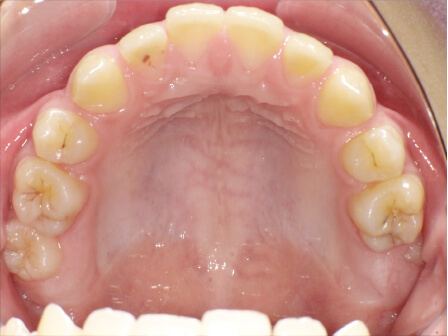

9歳

/

男性

相談内容

下の歯が重なっている。

カウンセリング・診断結果

myoからの移行

治療内容・方法

全額アライナー矯正

術後の経過・現在の様子

上下3〜3fix使用

治療のリスク

痛み・歯根吸収・歯肉退縮・虫歯・後戻り

費用・治療期間

880,000円、1年2ヶ月